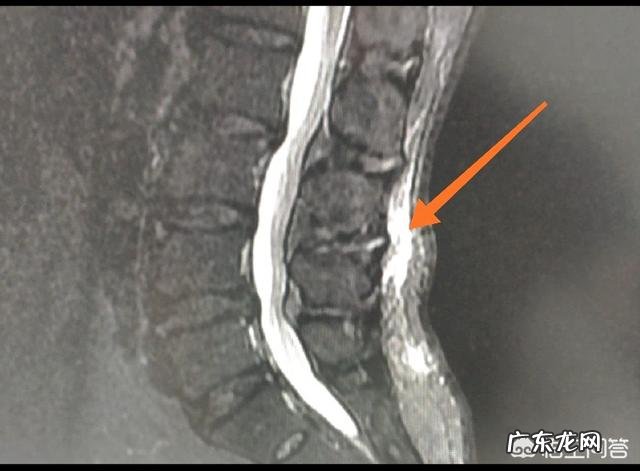

1、用力不当,拉伤:长时间的用力不当可能会导致后背肩胛部位的肌肉紧张,肌肉附着点发生慢性炎症,进而发生疼痛,这种疼痛多发生在一些需要进行搬运的工作人员,或者长期久坐的人,一般这种疼痛在热敷、休息后会有所缓解 。因用力不当导致的疼痛,大多可以在疼痛周围形成慢性炎症,比如下图的腰背部的浅筋膜炎,磁共振是可以看到的 。如果是应力性骨折那就要就诊脊柱外科 。

文章插图